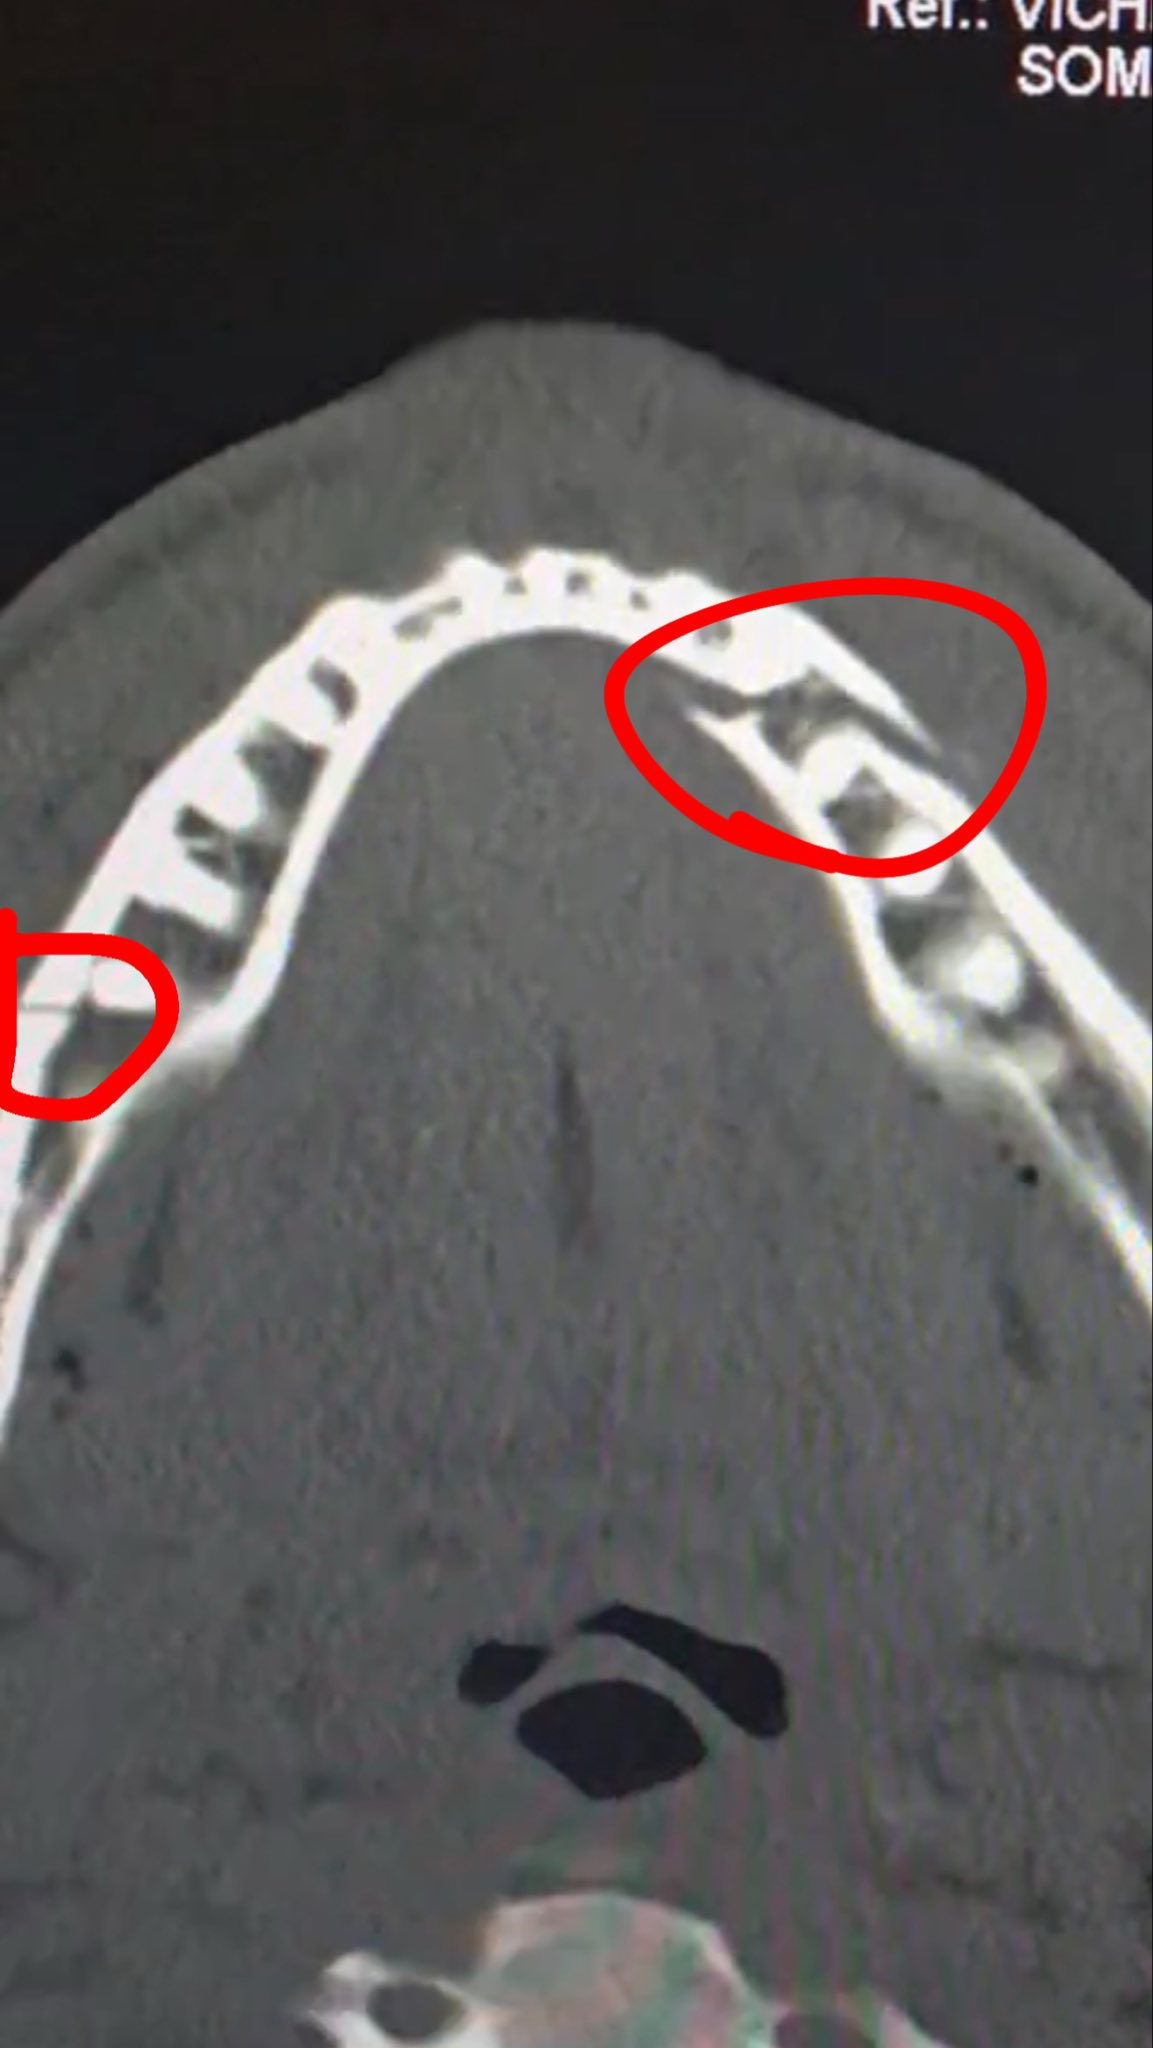

심지어 부상 상태는 꽤 심각한 것으로 알려졌다. 정밀검사 결과 폴의 턱에는 두 군데나 골절이 났다. 게다가 폴은 티타늄 플레이트를 두 개 삽입하고 일부 치아까지 뽑는 수술을 받은 것으로 파악됐다.